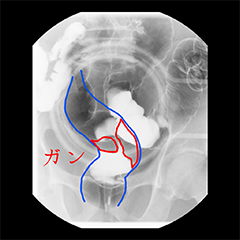

がんは早期に見つけることができれば治療できる可能性が高く、早期発見がとても重要です。

「疲れやすい」「体調がすぐれない」「食欲がない」「便の色がおかしい」など気になる症状があれば、「胃がん、大腸がん」の検診を受けましょう。